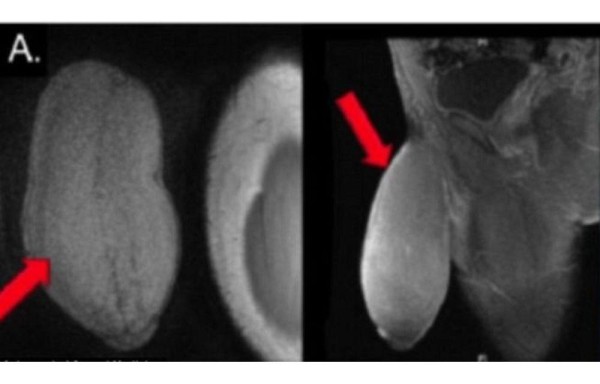

El adolescente había sufrido tres episodios de priapismo -una erección involuntaria-, que habían provocado una deformidad morfológica de su falo, dejándolo hinchado y deforme como un balón de rugby.

Según los médicos, en relajación, el miembro tenía una circunferencia de 25 centímetros (cm) parecido a un balón de fútbol americano. Luego de realizarle la operación el adolescente pasó dos días en el hospital y aunque los médicos no tomaron medidas del nuevo pene, el doctor Carrion aseguró que el joven se recupera favorablemente.